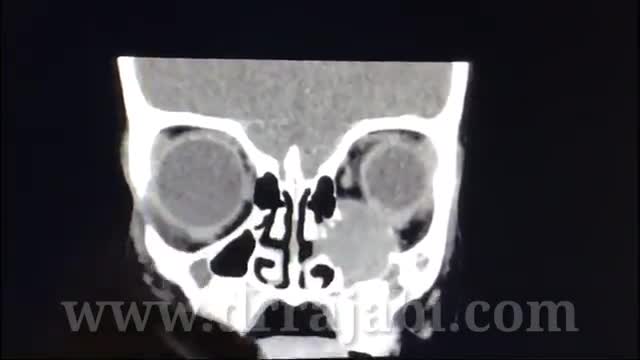

جراحی تومور با درگیری سینوس و کاسه چشم در کودک